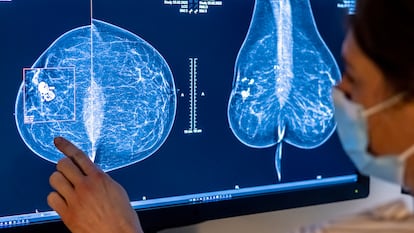

El cribado con ayuda de la IA mejora la detección temprana del cáncer de mama

Un ensayo demuestra que leer mamografías con su apoyo reduce la aparición de tumores agresivos, pero los autores niegan que sirva para sustituir personal sanitario